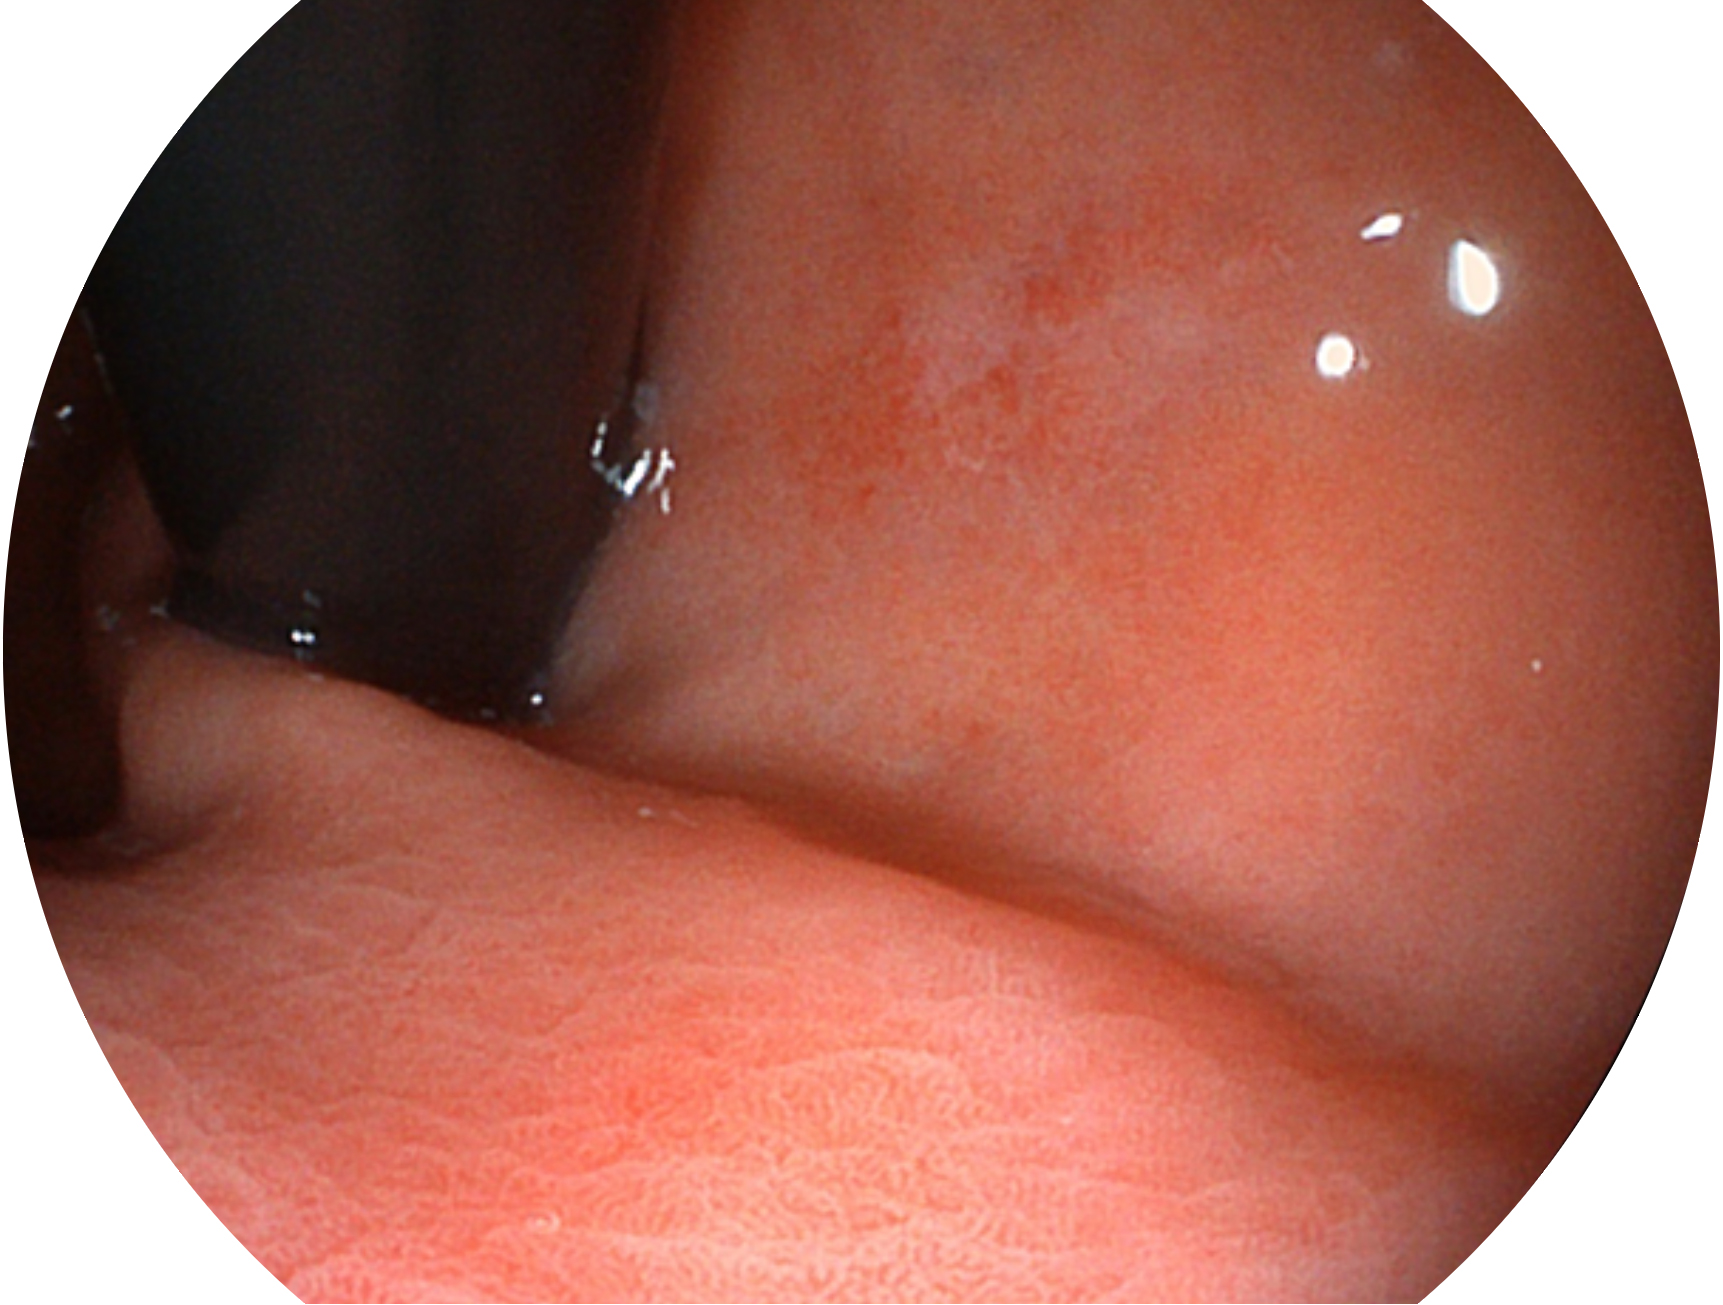

開立新開發(fā)的內(nèi)鏡染色技術(shù),主要是基于多波長LED 光源的開發(fā),VLS-55Q 四波長LED 光源是由四個(gè)不同顏色的LED光按照相應(yīng)照明模式所規(guī)定的特定發(fā)光比例進(jìn)行合束后形成,合束后形成的照明光的光譜由紅光、綠光、藍(lán)光及藍(lán)紫光這四個(gè)不同的波段范圍構(gòu)成。具有更高光譜自由度,通過光譜比例的控制,實(shí)現(xiàn)了聚譜成像技術(shù),英文全稱為“Spectral Focused Imaging, SFI”,縮寫為“SFI”和光電復(fù)合染色成像技術(shù),英文全稱為“Versatile Intelligent Staining Technology, VIST”,縮寫為“VIST”。